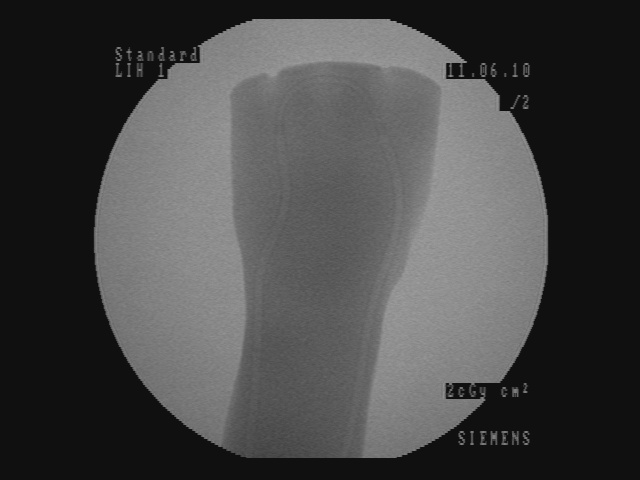

In Figure 5, for each scenario, one selected image Ilayerssubscript𝐼𝑙𝑎𝑦𝑒𝑟𝑠I_{layers} in the sequence can observed with different values of α𝛼\alpha, β𝛽\beta, γ𝛾\gamma and δ𝛿\delta. Each row i𝑖i corresponds to the sequence i𝑖i. From left to right, the layer visualized in Ilayerssubscript𝐼𝑙𝑎𝑦𝑒𝑟𝑠I_{layers} is getting closer to the X-ray source viewpoint. In the column (a), the furthest layer (the X-ray image) is displayed. In the column (b), the second layer (the background), in the column (c), the blending of the front layer with the background, in the column (d), the blending of the three layers and finally, in the column (e), the closest layer is shown. Additional images from the sequences can be visualized in the supplementary video where interaction between the layers by changing the blending values can be observed.

(a) (α,β,γ,δ)=(0,0,1,1)𝛼𝛽𝛾𝛿0011(\alpha,\beta,\gamma,\delta)=(0,0,1,1)

Refer to caption

(b) (α,β,γ,δ)=(0,1,0,0)𝛼𝛽𝛾𝛿0100(\alpha,\beta,\gamma,\delta)=(0,1,0,0)

(c) (α,β,γ,δ)=(0.4,0.6,0,0)𝛼𝛽𝛾𝛿0.40.600(\alpha,\beta,\gamma,\delta)=(0.4,0.6,0,0)

(d) (α,β,γ,δ)=(0.2,0.3,0.5,0.5)𝛼𝛽𝛾𝛿0.20.30.50.5(\alpha,\beta,\gamma,\delta)=(0.2,0.3,0.5,0.5)

(e) (α,β,γ,δ)=(1,0,0,0)𝛼𝛽𝛾𝛿1000(\alpha,\beta,\gamma,\delta)=(1,0,0,0)

(f) Inpainting

Figure 5: Per row i𝑖i, multi-layer image Ilayerssubscript𝐼𝑙𝑎𝑦𝑒𝑟𝑠I_{layers} of one selected frame in the sequence i𝑖i with different blending parameters (α,β,γ,δ)𝛼𝛽𝛾𝛿(\alpha,\beta,\gamma,\delta)

Similar to results from Habert et al. [6], the images resulting from synthesization are not as sharp as a real video image. The area synthesized by our algorithm is approximately 20 cm ×\times 20 cm (C-arm detector size), which is small compared to the wide-angle field of view from the Kinect v2. Reduced to the area of synthesization, the video and depth from Kinect is not of high resolution enough for sharper results. More specialized hardware with smaller field of view and higher resolution RGBD data would solve this problem. Moreover, several artifacts can be seen around the hand and surgical instruments in the synthesized image due to high difference and noise in depth in the RGBD data from the 2 cameras. However, our results demonstrate that our method is working well, since the incision line and cross drawn on the hand model and patient hand are perfectly visible in the recovered background image and can be seen in transparency through the hands and surgical tools in the images of Figure 5-column (c) and (d). In the scalpel sequence (sequence 6) in Figure 5-column (b), it can be seen that the tip of the scalpel is considered as background, this is due to the margin of few centimeters used for background segmentation. In this image, the scalpel is actually touching the skin.